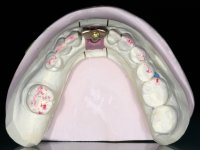

With the implant osteo-integrated with did an impression (open-tray technique) and the dental technician started the construction of a gold framework. The use of an abutment made of a gold alloy allowed us to do a framework with a perfect fit.

During the framework try-in, the color survey was done in order to proceed with the ceramics placement, with a crown and gingiva-components.